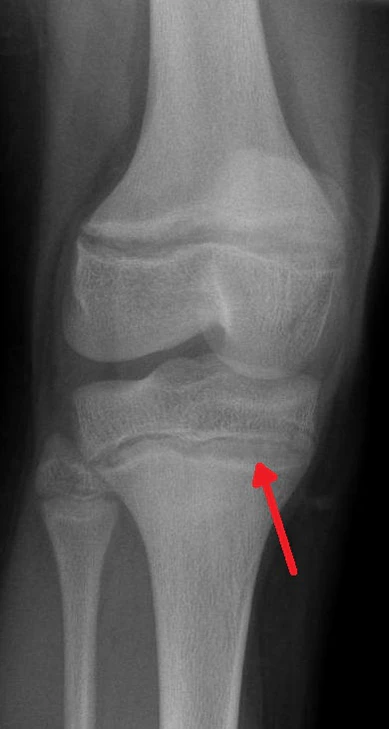

Одним из диагностических признаков отравления свинцом является так называемая «свинцовая кайма»[6]. Дальнейшее развитие науки позволило сформулировать требования по охране труда при работе со свинцом[7], обязательные для выполнения работодателем. Концентрация свинца и протопорфирина цинка в крови строго контролируется, через медицинское обследование.